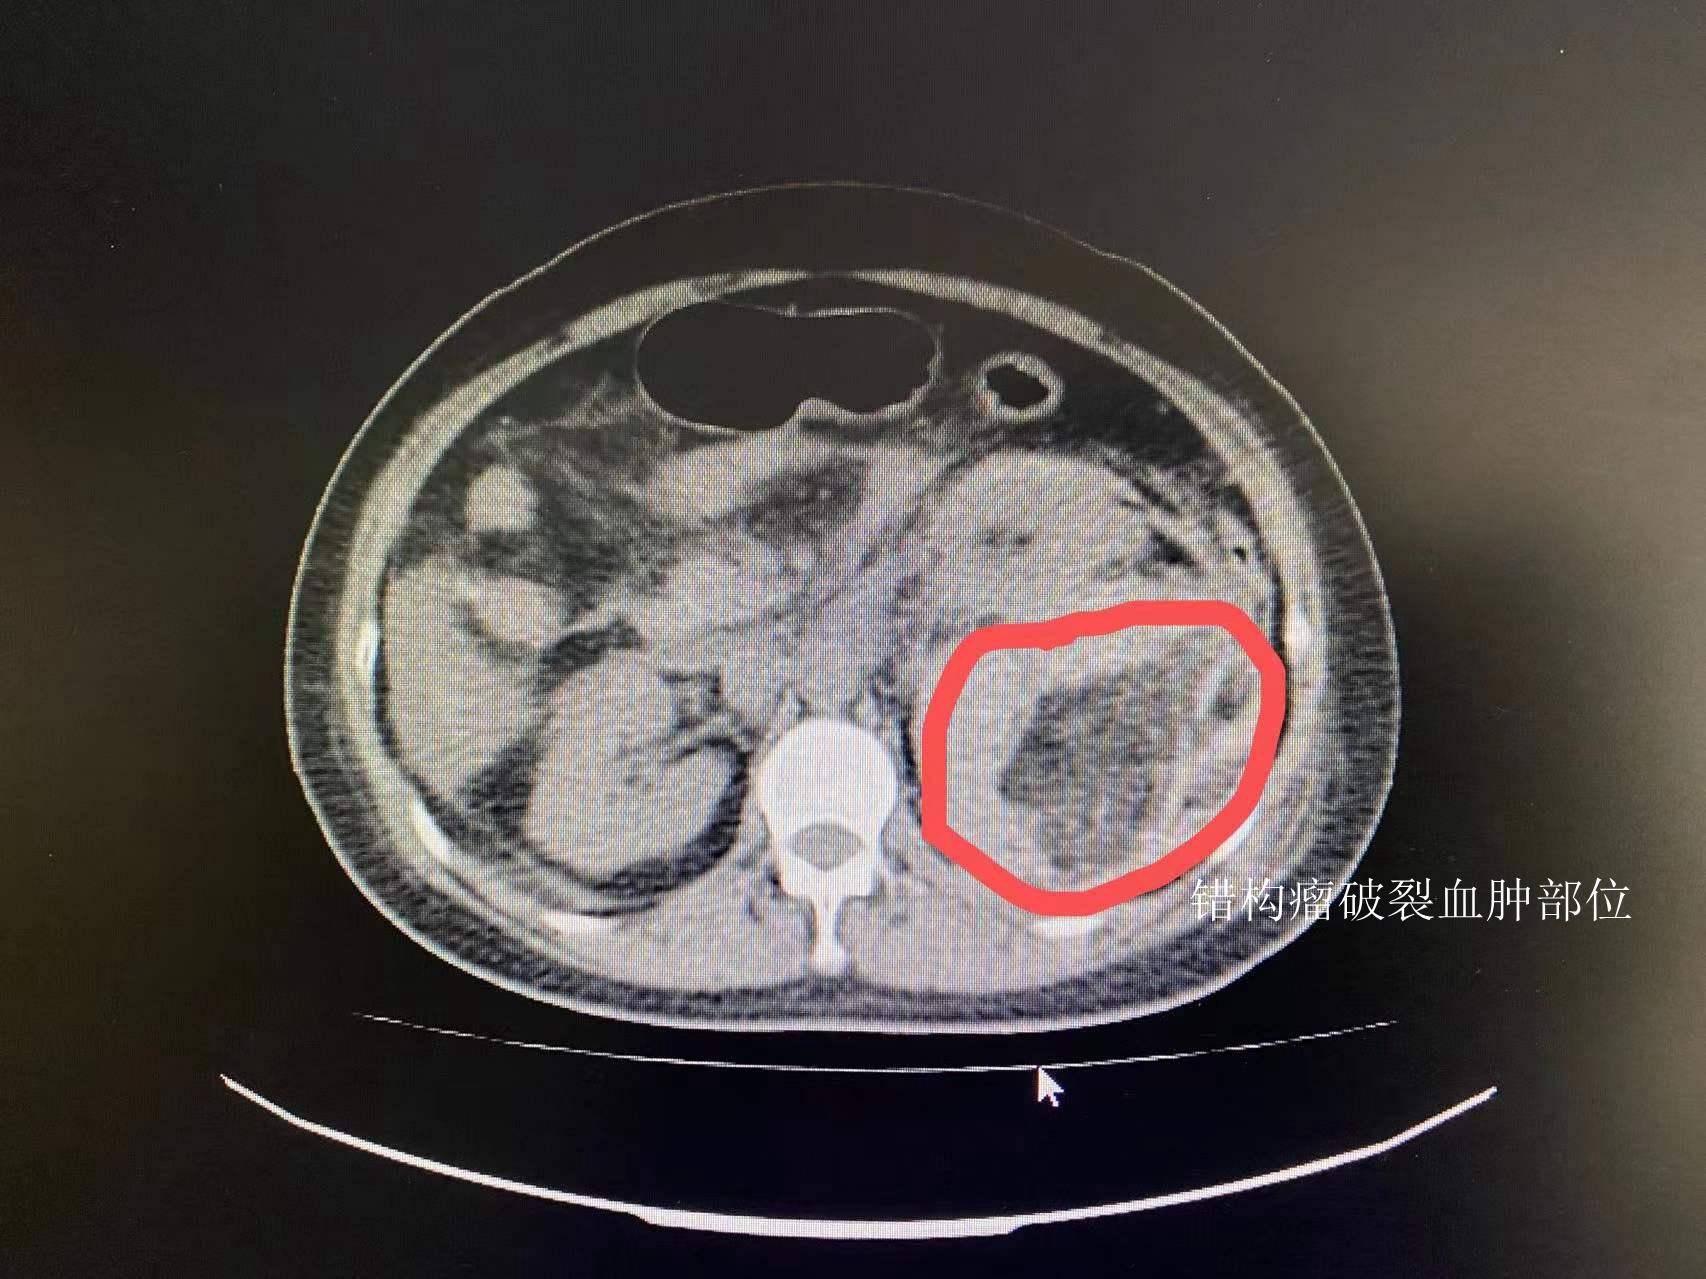

此患者为老年男性,突发腹痛2天,急诊ct检查提示右肾巨大错构瘤并破裂

图片尺寸994x1354